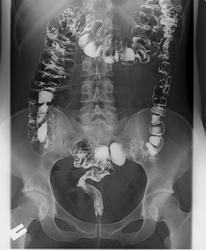

Возможно, есть изменения по-типу болезни Гирсшрунга, но неубедительно. Купол слепой кишки как бы кисетообразно подтянут по медиальному контуру, возможно есть поражение баугиниевой заслонки. Попробуйте провести энтерографию.

Никакой значимой патологии на представленных снимаках четко не определяется. То, что указано стрелками - м.б. просто спазм, м.б. и изъязвление, но не очень доказательно.

Колоноскопом не смогли пройти глубоко. Интересует сигмовидный отдел.

Извините, коллега, при колоноскопии не смогли пройти сигмовидную кишку?

на мой взгляд не все изгибы разведены (может не все снимки представлены), нет тугого наполнения кишки, большая часть снимков с двойным контрастированием, да и без скопии сложно оценивать изменения указанные стрелками. а в целом без явных стойких сужений и дефектов наполнения.